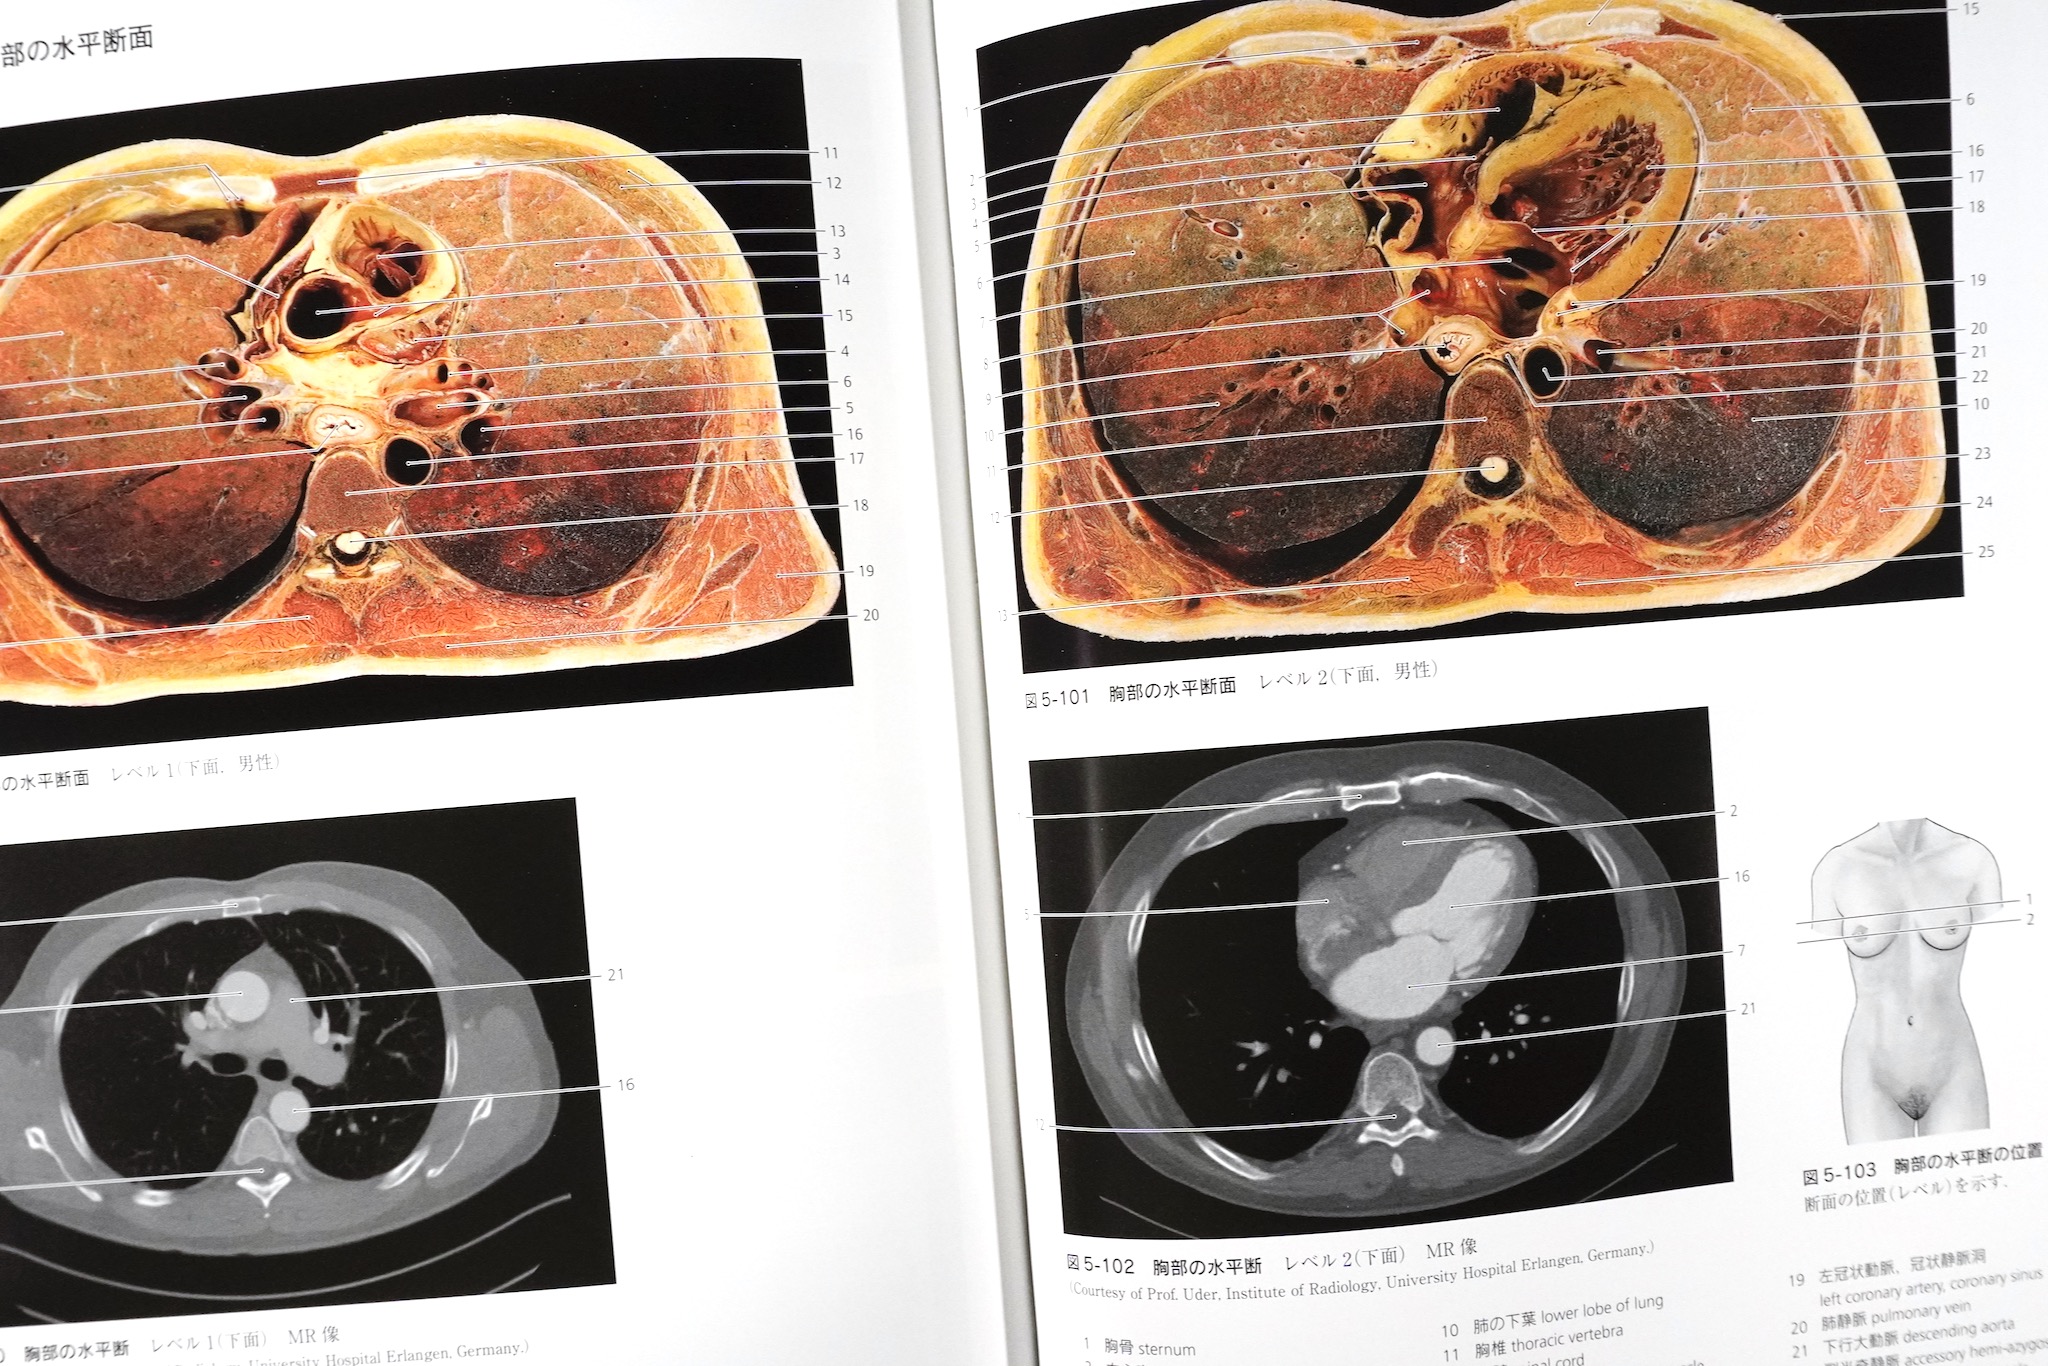

胸部の横断標本と胸部CT

CT画像が差し替えられた:左が第8版、右が第9版。CTのスライス位置を解剖標本の切断面に合わせた。第8版のキャプションの誤りも正された(MRではなくCT)